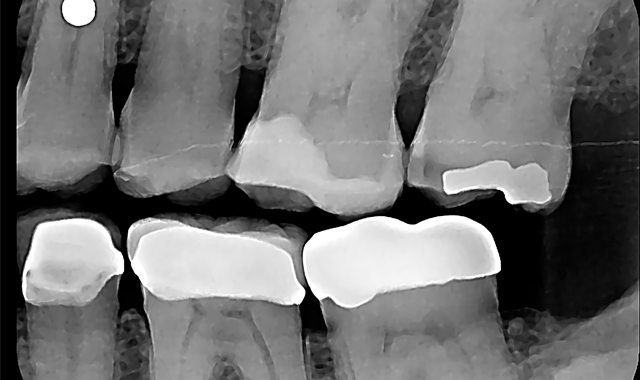

A pre-operative diagnostic radiograph showed no endodontic pathology. She is in excellent periodontal health (Fig. 1). Oral evaluation of the patient indicated that the palatal cusp of #15 fractured subgingivally to the level of the alveolar crest (Fig. 2).

Fig. 1 Fig. 2